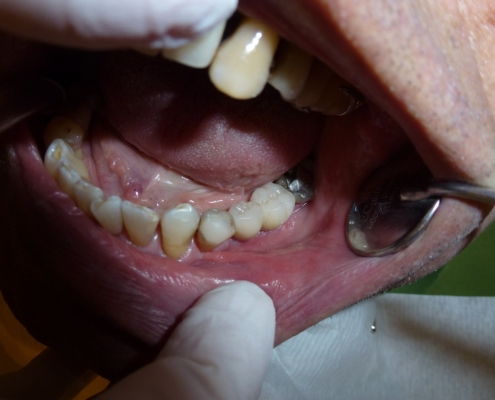

Eine gründliche Untersuchung, ein ausführliches Beratungsgespräch, in dem wir gerne alle Ihre Fragen beantworten, sowie eine transparente Therapie- und Kostenplanung im Falle einer Amalgamsanierung betrachten wir als Voraussetzungen für optimale Behandlungsergebnisse.

Amalgam ist auch heute in Deutschland noch das Füllungsmaterial Nummer eins, welches von den Krankenkassen als Regelversorgung im Füllungsbereich gilt.

Aber was ist Amalgam eigentlich, warum gehen hier die Meinungen so weit auseinander, warum wird es in einigen Praxen fast ausschließlich verwendet und in anderen gar nicht mehr, warum wird es täglich in etliche Zähne, also in den Körper eingebracht, muss aber als „Sondermüll“ entsorgt werden?

Hier wollen wir einige Fragen beantworten und Ihnen erläutern, wie wir mit Amalgamfüllungen, welche bei uns ausschließlich entfernt werden umgehen.